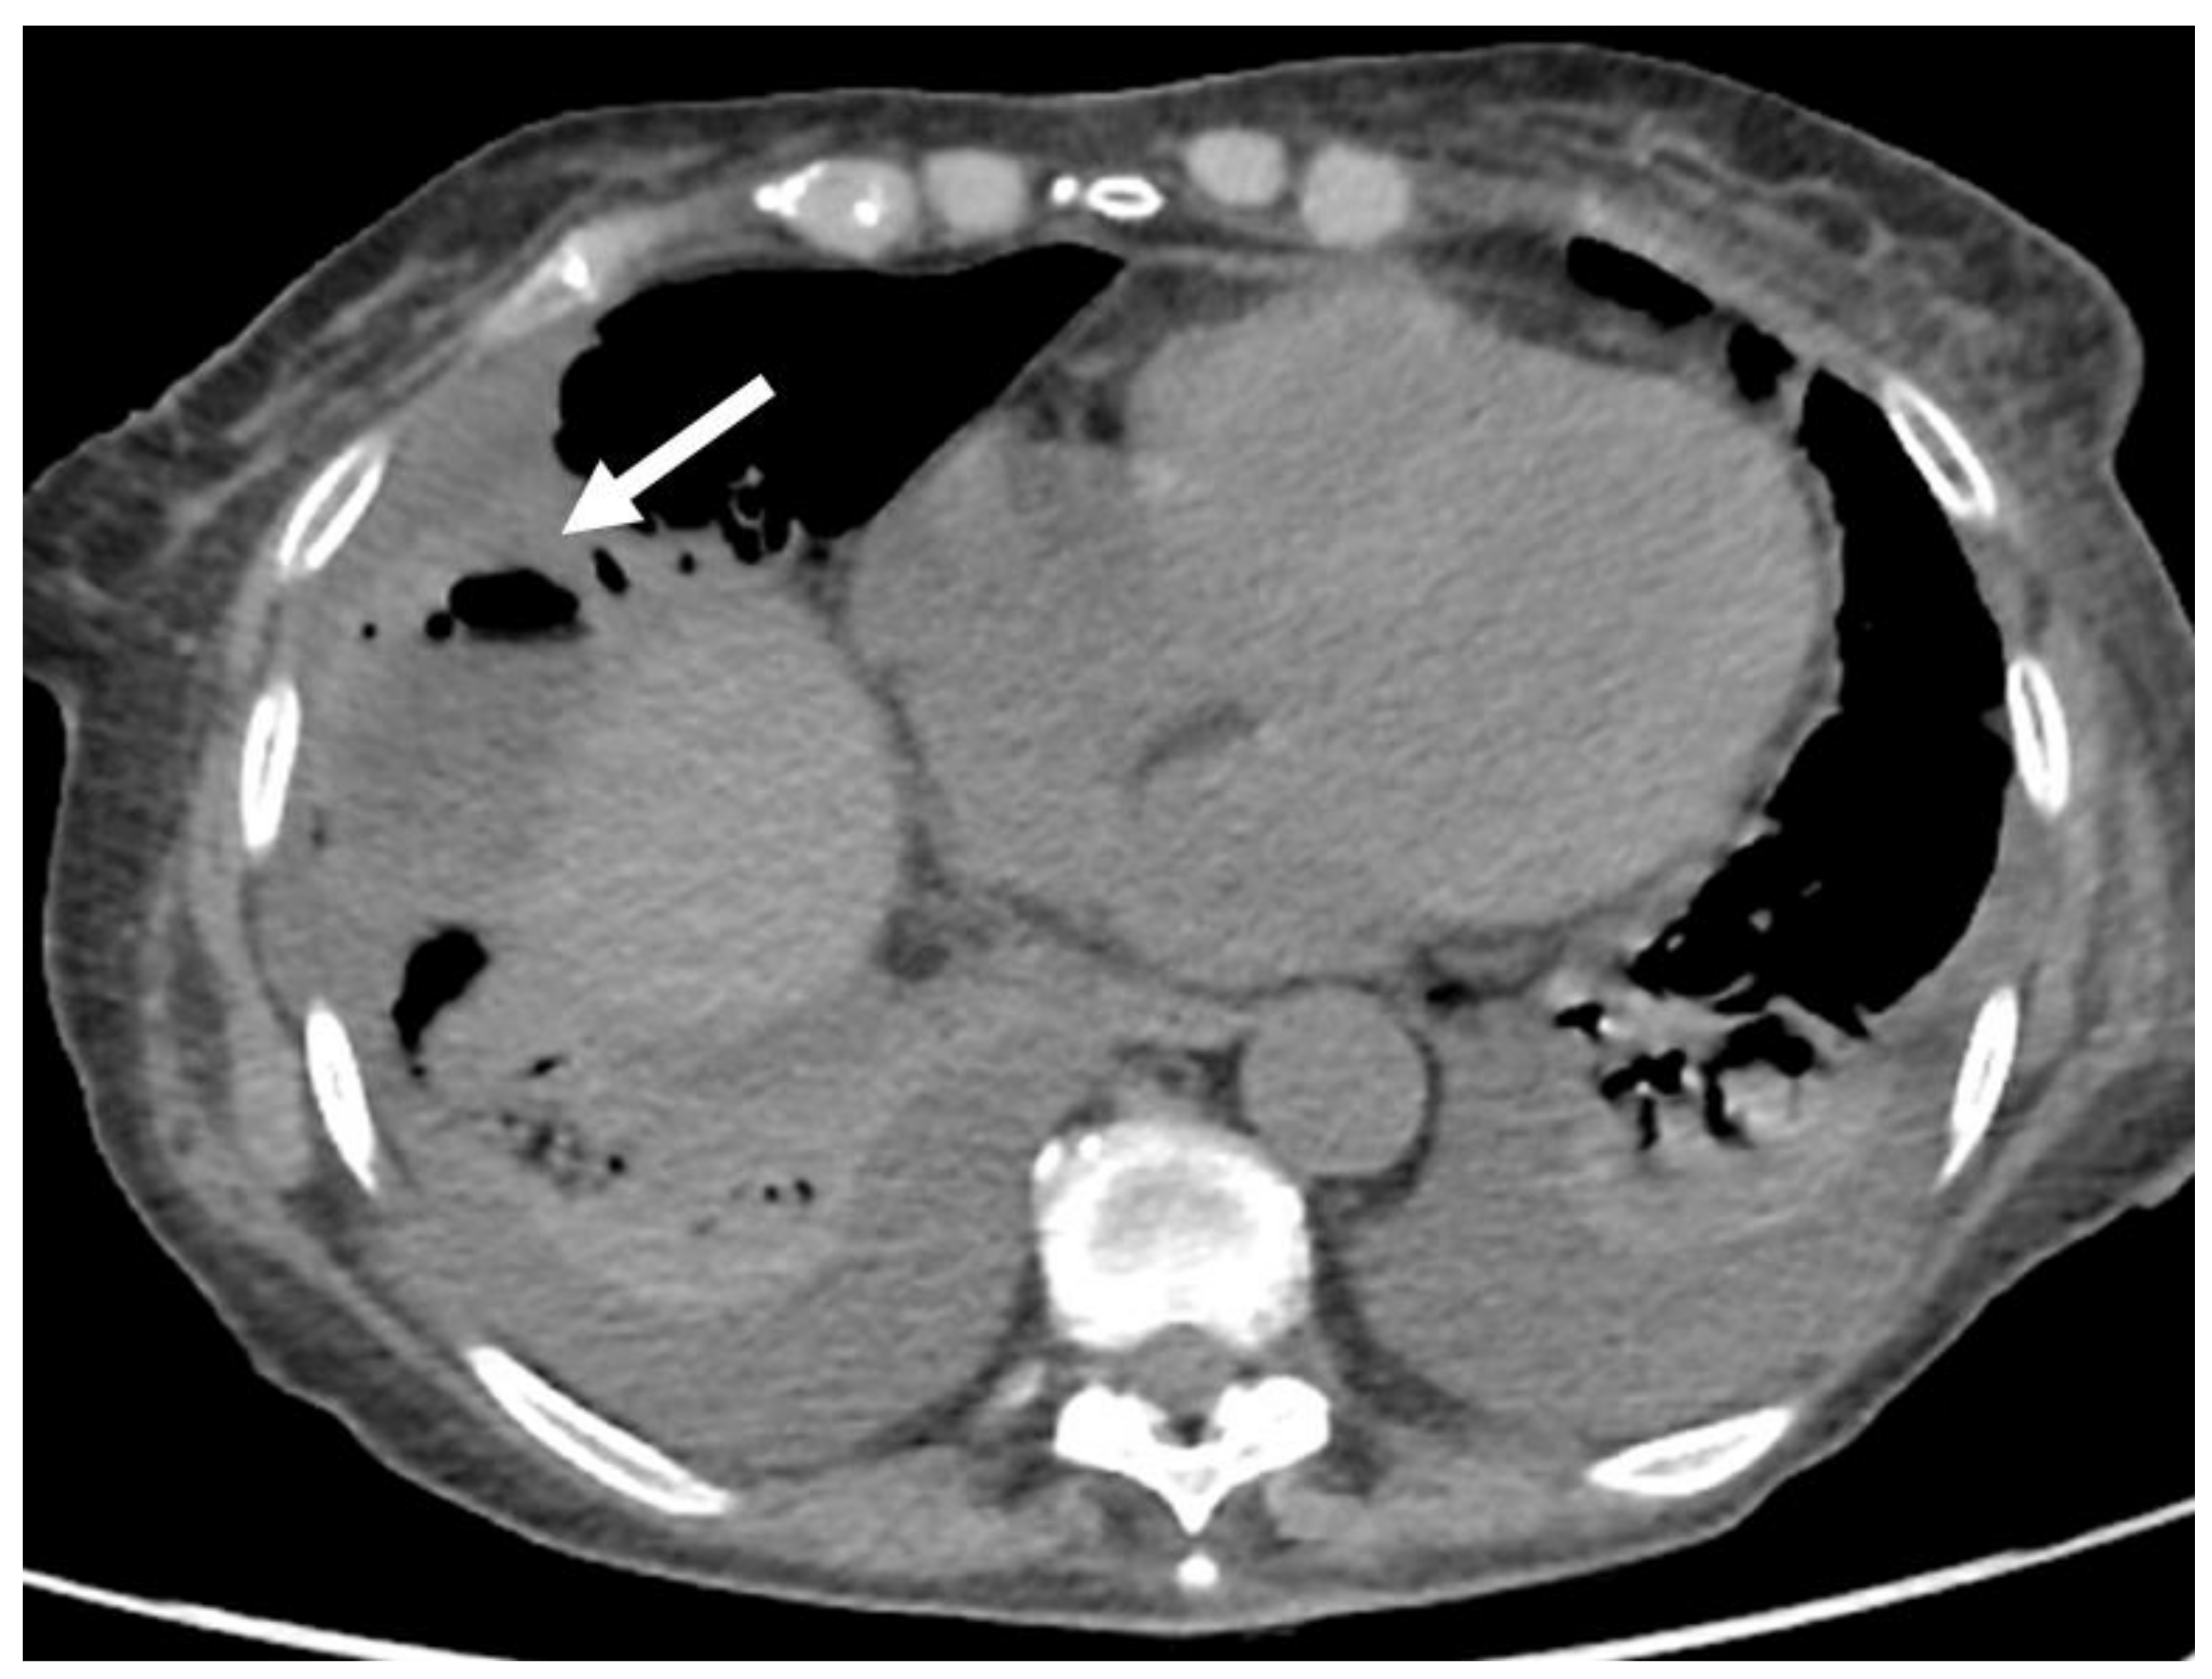

- Granata, V.; Grassi, R.; Fusco, R.; Belli, A.; Cutolo, C.; Pradella, S.; Grazzini, G.; La Porta, M.; Brunese, M.C.; De Muzio, F.; et al. Diagnostic evaluation and ablation treatments assessment in hepatocellular carcinoma. Infect. Agents Cancer 2021, 16, 53. [Google Scholar] [CrossRef] [PubMed]

- Izzo, F.; Granata, V.; Grassi, R.; Fusco, R.; Palaia, R.; Delrio, P.; Carrafiello, G.; Azoulay, D.; Petrillo, A.; Curley, S.A. Radiofrequency Ablation and Microwave Ablation in Liver Tumors: An Update. Oncologist 2019, 24, e990–e1005. [Google Scholar] [CrossRef] [Green Version]

- Fang, C.; Cortis, K.; Yusuf, G.T.; Gregory, S.; Lewis, D.; Kane, P.; Peddu, P. Complications from percutaneous microwave ablation of liver tumours: A pictorial review. Br. J. Radiol. 2019, 92, 20180864. [Google Scholar] [CrossRef]